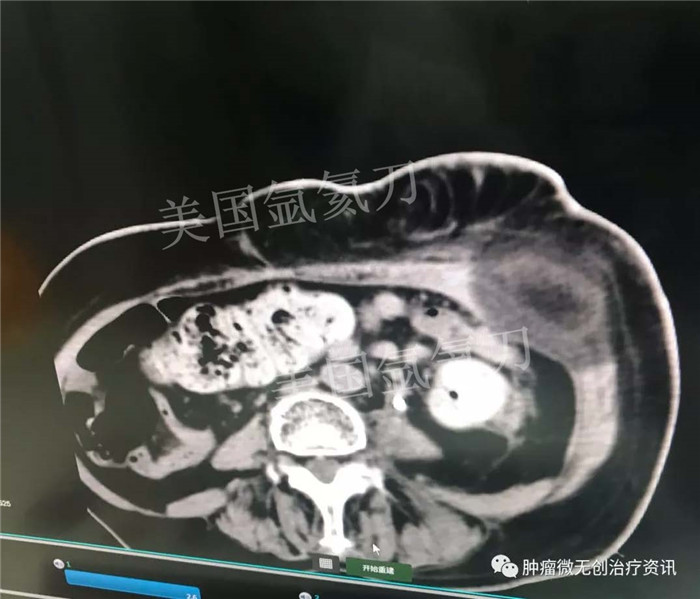

中美国际肿瘤医院氩氦刀冷冻消融治疗子宫颈癌左髂骨内侧转移病灶

患者女性,63岁,宫颈癌术后1年余。左髂骨内侧转移放、化疗后,患者左下肢疼痛持续无改善,今为求进一步治疗,就诊于中美国际肿瘤医院。结合患者情况,行氩氦刀冷冻消融治疗。此次治疗主要以止痛为主。